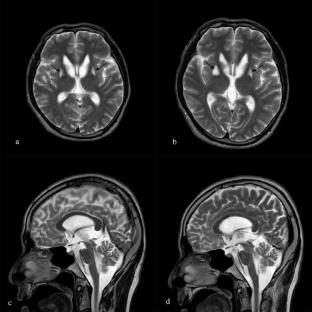

Co-occurrence of Wilson’s Disease and Spinocerebellar Ataxia Type 3 in a Chinese Patient

肝豆状核变性与脊髓小脑性共济失调3型共发1例。